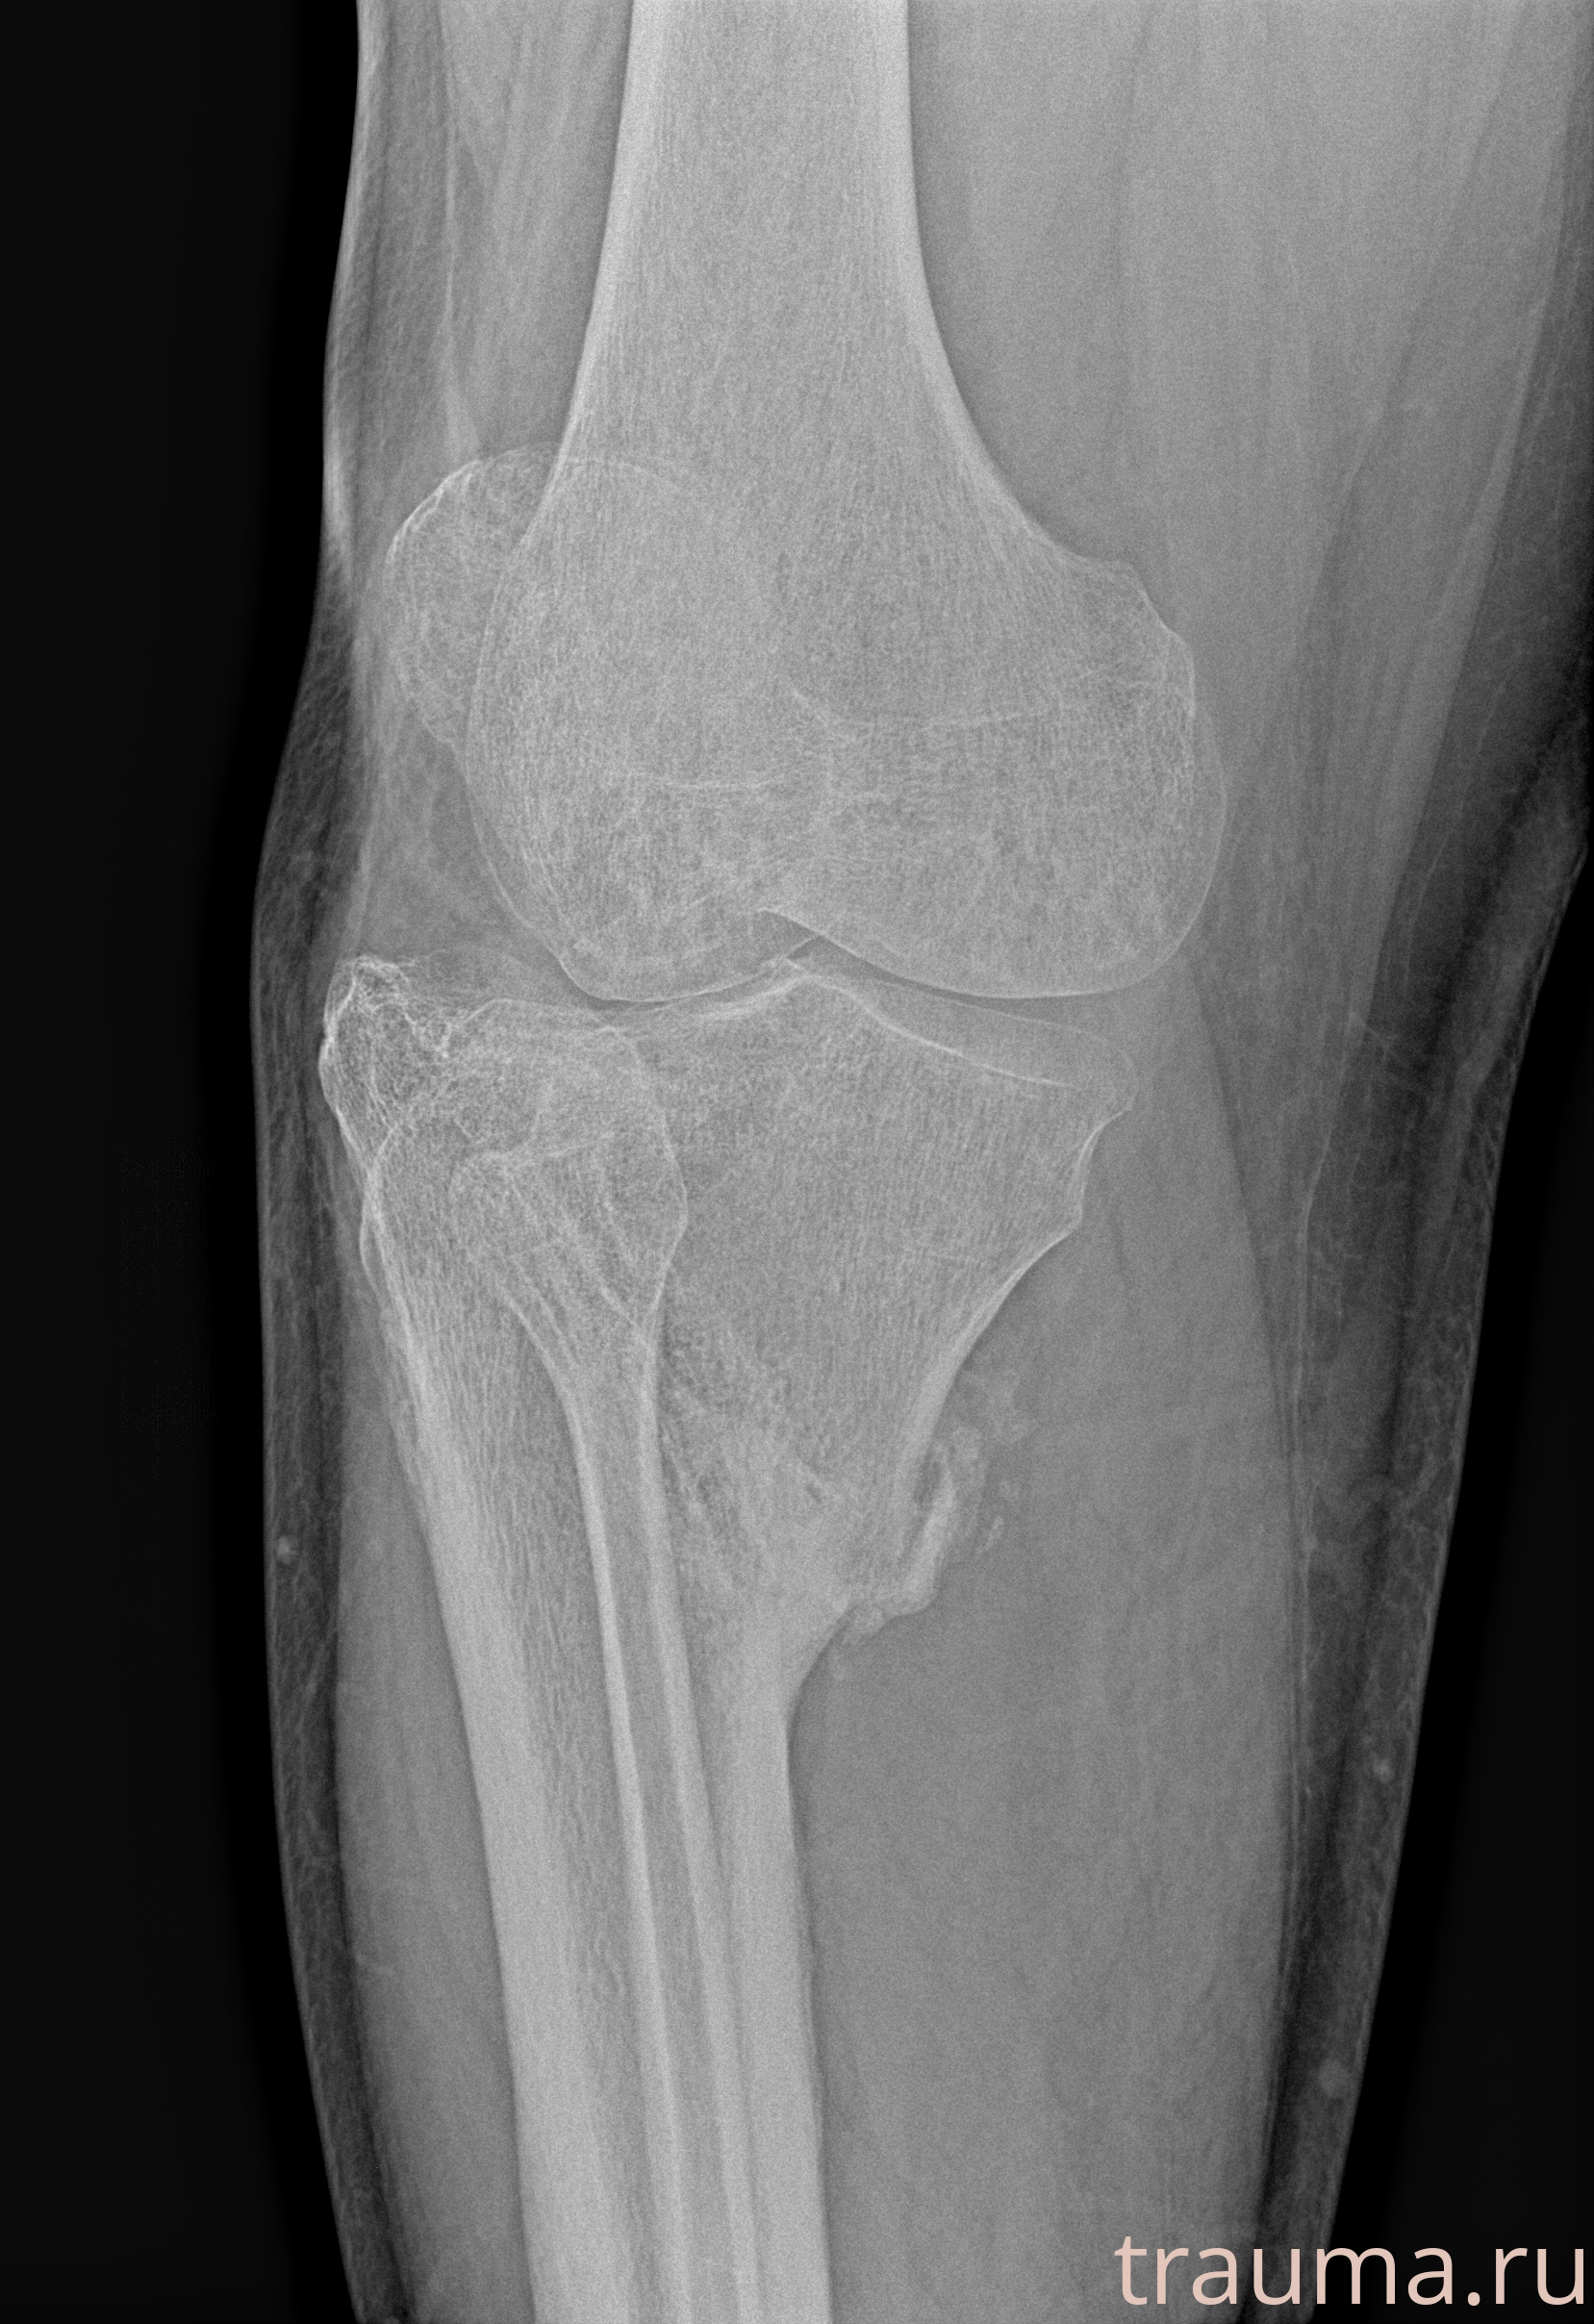

Рентгенограммы

Рентген на дому: по вашему адресу приезжает врач-рентгенолог, травматолог-ортопед с мобильным рентгеновским аппаратом, проводит диагностику травмы или заболевания, делает необходимые рентгенограммы, дает рекомендации по дальнейшему лечению. Получить качественные снимки в домашних условиях возможно благодаря уникальной методике, разработанной МосРентген Центром для института  Склифосовского